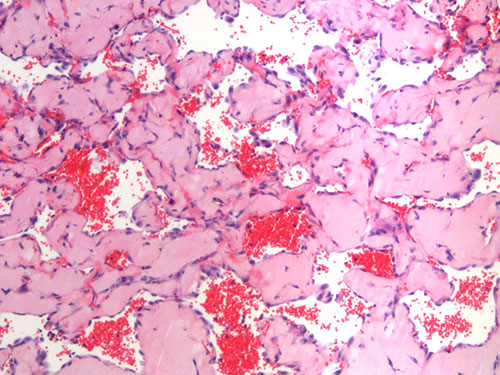

1) Diagnostic biomarker identification and analysis for vascular anomalies

2) Human patient-derived cell xenograft models of vascular anomalies

3) Mouse models of vascular anomalies

“Pathogenesis and Treatment of Kaposiform Lymphangiomatosis“

The major goals of this project are to test the hypothesis that the somatic p.Q61R NRAS mutation in human endothelial cells drives the pathogenesis of KLA and elevated production of ANGPT2.